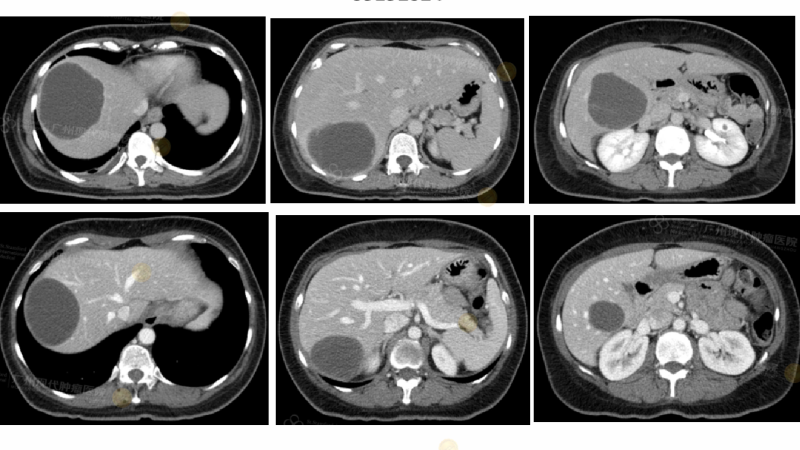

基于精准分析发现该患者为HER2阳性、PD-L1阳性并伴有功能失调状态。这位曾接受全乳切除术并延期化疗的患者,在2024年出现脊椎、肝脏和肺部多发转移。基于此,个性化治疗方案巧妙结合了靶向药和生物疗法,并辅以持续的代谢与生理支持。最终,患者成功获得完全代谢缓解(CR),并恢复了良好的生活质量。

(CT显示肿瘤病灶完全消失)

案例二:难治性卵巢间质肉瘤患者

这位48岁的卵巢间质肉瘤患者,在经历多线化疗失败后,已出现肝脏大部及双肺转移。精准诊断显示其肿瘤存在VEGFR2、FGFR3、c-MET等高表达特征,并伴有显著的生物功能紊乱。采用生物疗法、靶向药物联合整合支持治疗后,患者肿瘤迅速缩小,并进入缓解期。